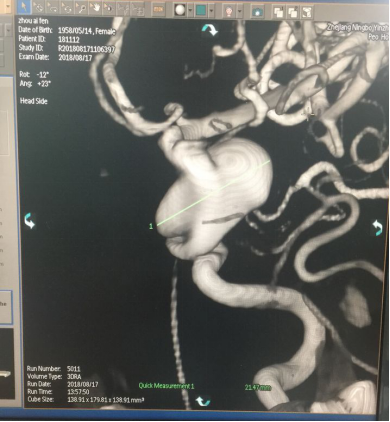

3D重建